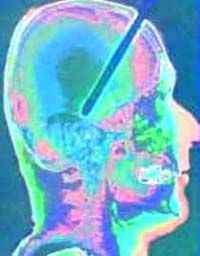

Blinde

sehen, Taube hören, Lahme gehen

Neurotechnische

Implantate und Gehirndesign

An der Schittstelle von Biologie und KI-Technologie werden Neuro-Implantate entwickelt, mit denen verloren gegangene Sinne ersetzt werden können.

Viele Anwendungen sind heute bereits Realität oder stehen kurz davor. Schon in den nächsten Jahrzehnten können Patienten mit amputierten Gliedern

oder Nervenverletzungen

ihren Tastsinn oder Sehsinn zurückerhalten.

Wissenschaftler sprechen schon heute von einem Gehirndesign und haben Visionen von Cyber-Lebewesen (bdw 1/2000).